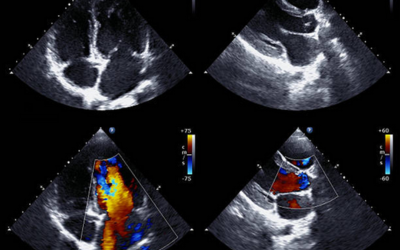

Echocardiography (2D Echo)

The most frequent test for diagnosing ASD. A non-surgical test that employs the use of ultrasound waves to produce images of the heart, which indicate the size of the defect and how it impacts blood circulation.